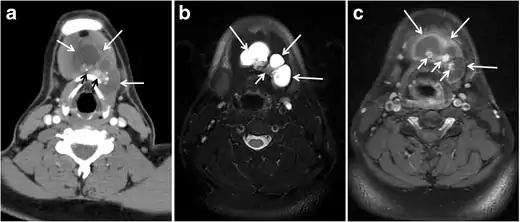

Thyroid calcifications on a CT scan can be seen in both benign and malignant thyroid lesions. Sonographic examination of the thyroid can differentiate between micro-calcifications, which are highly associated with papillary thyroid carcinoma, and eggshell calcifications, which favour a benign process such as colloid cysts (Figs. 1 and 2). In a retrospective review of preoperative CT scan, 35% (135 of 383) of the patients had detectable intrathyroidal calcifications. Among them, 48% had a histopathologically proven thyroid cancer. Calcified nodules had a significantly higher incidence of thyroid cancer and lymph node metastases. The incidence of thyroid cancer among nodules with different calcifications patterns was 79% of nodules with multiple punctate calcifications, 58% of nodules with a single punctate calcification, 21% of nodules with coarse calcification, and 22% of nodules with peripheral calcification. Most of the single calcified nodules were malignant. However, this did not include patients with ITNs and the sample is skewed towards malignancy. Another study evaluated the presence of ITNs on CT scans and found that 12% of thyroid nodules were calcified, with no significant correlation between malignant or potentially malignant histology and punctate calcifications. As a result, some researchers believe that calcification per se is not a suspicious CT sign, and have suggested that calcified thyroid nodules on CT scans should be treated the same as non-calcified nodules.[1]

Fig. 1. An incidentally discovered colloid nodule with calcification, shown on CT scan of a 58-year-old female patient. a Non-enhanced axial CT scan of the neck demonstrates a coarse calcification at the left thyroid inferior pole. b Sagittal grey scale ultrasound of the thyroid demonstrates a heterogeneous nodule with a predominant cystic component. Calcification was not seen in the ultrasound, probably due to its lower location in the superior mediastinum.[1]

Fig. 2. A 51-year-old female patient post left hemithyroidectomy, with incidentally discovered a right thyroid colloid nodule on CT scan. an Enhanced axial CT scan of the neck demonstrates a well-defined, hypodense right thyroid nodule (white arrow) with no internal calcifications or cervical lymphadenopathy. b Transverse greyscale thyroid ultrasound demonstrates a well-defined, hypoechoic right thyroid lobe nodule with a central echogenicity including comet tail (ring down) artefacts (white arrow). No vascularity (not shown) or calcifications were detected.